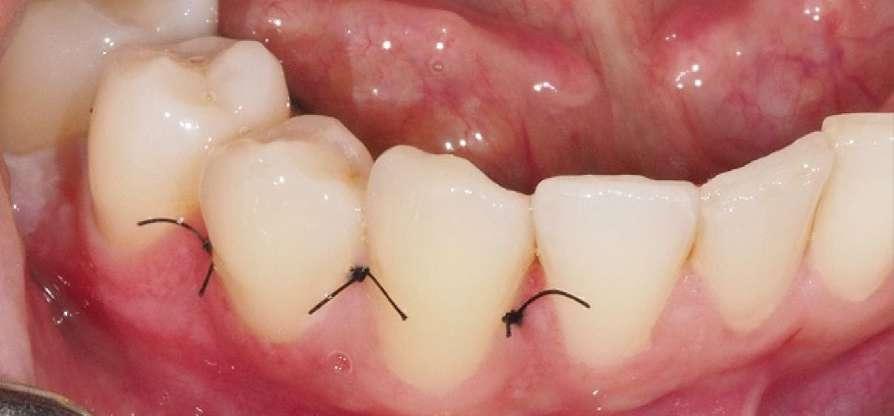

Tal y como se puede observar en las imágenes (Fig. 3 y 4) se realizó una incisión sulcular siguiendo el surco gingivodentario lingual sin descargas para despegar un colgajo a espesor total que facilitó un campo quirúrgico suficiente como para poder realizar la ostectomía hasta descubrir la corona del diente (Fig. 5).

La ostectomía se realizó de manera cuidadosa, tanto con el colgajo y las estructuras del suelo de boca, como con los dientes adyacentes y sus raíces. En este caso el diente no requirió odontosección, por lo que su exodoncia pudo ser completada usando un botador recto y unas pinzas adson para su retirada del alveolo (Fig. 6).

Una vez finalizada la intervención se procedió a realizar sutura interpapilar con sutura monofilamento 5/0 (Fig. 7 y 8).

3 4 5 6

Figuras 1 y 2. Situación inicial y anestesia. Figuras 3 y 4. Incisión y despegamiento del colgajo lingual festoneado.

1 2

Figuras 5 y 6. Ostectomía y exodoncia con botador tipo elevador recto.